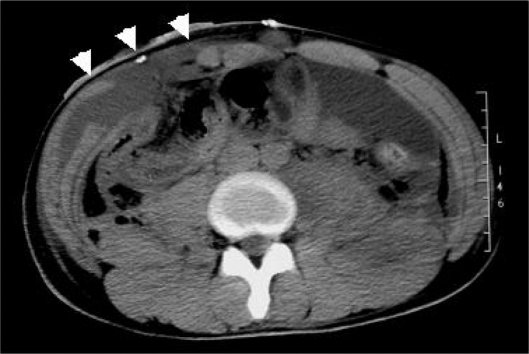

Для диагностики данного осложнения и поиска абсцессов в брюшной полости рекомендуется использовать ультразвук и компьютерную томографию. Если абсцесс образовался как осложнение после аппендицита у женщин, характерна его тазовая локализация. Тогда его наличие можно определить при помощи вагинального обследования.

Выше представлено КТ при образовании абсцесса передней брюшной стенки.